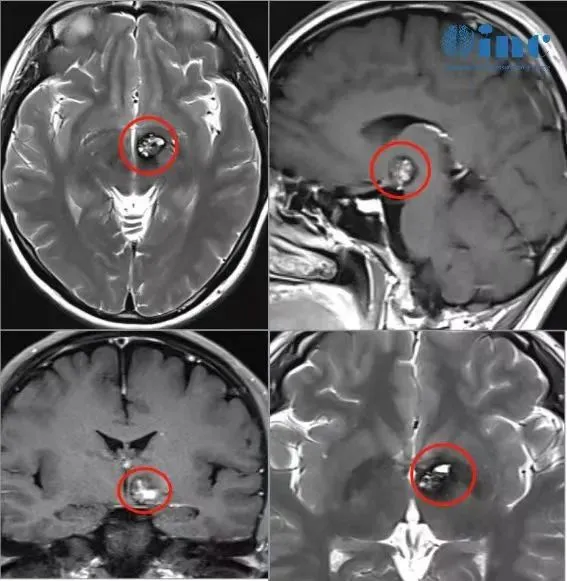

然而,头颅MRI影像并未带来安心,反而给予了沉重一击。报告单上呈现的冰冷文字与胶片上清晰的阴影共同显示:

左侧基底节-丘脑区域存在占位性病变,考虑为海绵状血管瘤,并伴有瘤内出血。

“丘脑具体位于何处?海绵状血管瘤属于何种疾病?发生出血是否危险?”文文与家人在诊室内接连提出疑问。医生的回答让她彻底明白了自身所面临的处境:

“丘脑区域手术风险极高,一旦进行手术操作可能导致严重后果,瘫痪的可能性非常大。”

丘脑体积虽小如橄榄,却是大脑信息交互的核心枢纽。全身的痛觉、温觉、触觉等所有感觉信号均在此进行中继与上传;大脑发出的每一项运动指令也在此进行整合与下达。其周围紧密环绕着控制肢体运动的神经纤维束、视觉传导通路以及负责记忆、情感的高级认知功能区。更深层区域则是维持心跳与呼吸的脑干生命中枢。

在该区域实施手术,无异于在最精密的“芯片”中央使用手术刀进行拆除作业。任何细微的偏差均可能引发偏瘫、失明、失语,甚至导致植物状态。